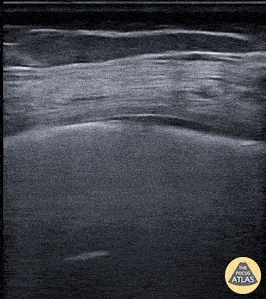

Lung ultrasound image taken from a patient who tested positive for the novel coronavirus (COVID-19). Note the presence of clustered B-lines, a thickened and irregular pleura, and small subpleural consolidations. Marco Garrone, Emergency Medicine Physician @drmarcogarrone